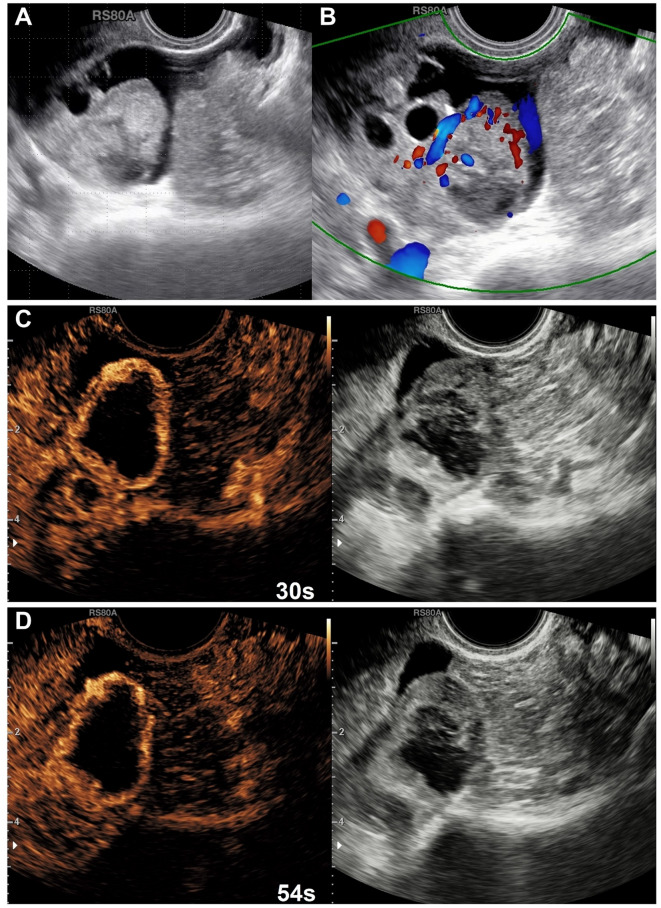

Purpose: Differentiating between benign and malignant ovarian masses remains a significant clinical challenge. Although the Ovarian-Adnexal Reporting and Data System Ultrasound Version 2022 (O-RADS US v2022) provides standardized terminology and high sensitivity, its specificity remains suboptimal, potentially leading to overdiagnosis and overtreatment. Incorporating tumor vascularity evaluation via contrast-enhanced ultrasound (CEUS) and serum tumor markers like CA125 may enhance diagnostic accuracy and help guide clinical management more effectively.

Methods: A retrospective study of 909 patients with adnexal masses undergoing ultrasound at Sichuan Cancer Hospital from May 2022 to March 2025 was conducted. O-RADS US v2022, CEUS scores, and CA125 levels were analyzed to develop a novel scoring system (OCC-US). Diagnostic performance was evaluated using ROC curves, logistic regression, and inter-observer agreement analysis. Additionally, a temporally independent validation cohort was retrospectively assembled to assess the generalizability and diagnostic accuracy of the OCC-US model.

Results: A total of 609 patients were enrolled in the development cohort between May 2022 and May 2024. ROC analysis identified O-RADS US v2022 ≥ 4, CEUS score ≥ 4, and CA125 ≥ 37.815 U/mL as independent predictors of malignancy. Based on these variables, the OCC-US scoring system was developed, assigning 2 points each for O-RADS ≥ 4 and CEUS score ≥ 4, and 1 point for CA125 ≥ 37.815 U/mL (total score range: 0-5). OCC-US achieved the highest diagnostic performance with an AUC of 0.916, outperforming OC-US (0.891), CEUS (0.877), O-RADS US v2022 (0.871), and CA125 (0.784). It significantly improved specificity (85.4% vs. 71.5%, P < 0.001) while maintaining high sensitivity (84.9%), reducing the false-positive rate from 23.1% (O-RADS US v2022) to 6.2%. OCC-US also reduced unnecessary surgical recommendations from 300 (O-RADS US v2022) to 243 (P < 0.001). Inter-observer agreement was excellent (κ = 0.840, P < 0.001), indicating high reliability. In the temporally independent external validation cohort (300 patients enrolled between June 2024 and March 2025), the OCC-US model maintained stable diagnostic performance, with an AUC of 0.867.

Conclusion: The OCC-US model enhances diagnostic specificity while maintaining high sensitivity, optimizing risk stratification and surgical decision-making. Further multi-center prospective studies are needed for broader validation.